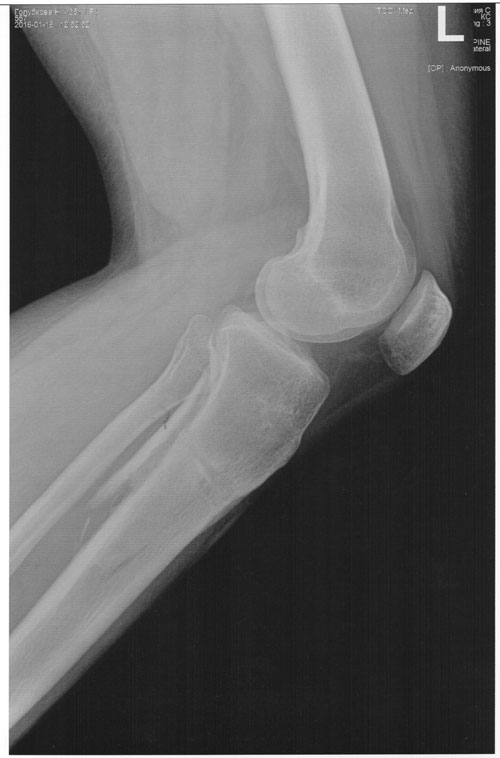

Отправляю вам контрольные рентген-снимки и фото ножек. Со дня снятия прошло 50 дней.

Здравствуйте, Наталья! По рентгену, всё отлично! разрешено всё без ограничений! Исключить: беременность в течении первых 6 месяцев.